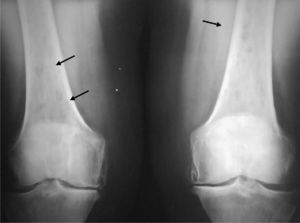

En la radiología simple se evidenciaron lesiones osteolíticas, sin bordes esclerosos de distintos tamaños y sin destrucción cortical en fémures (fig. 1), húmeros (fig. 2), parrilla costal, clavículas y cráneo (fig. 3), sin captación gammagráfica (Tc99) de las mismas.

Ante el diagnóstico diferencial de dichas lesiones (mieloma múltiple, metástasis de carcinoma de mama, pulmón, riñón y tiroides, enfermedad granulomatosa, mastocitosis, enfermedad de Gaucher) se realizó un aspirado de médula ósea que mostró una infiltración por células plasmáticas dismórficas del 23% y permitió confirmar el diagnóstico de MM no secretor (tabla 1).